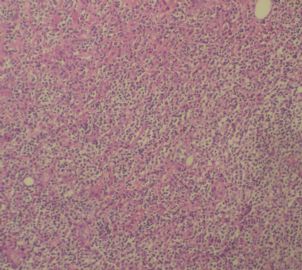

姓    名: ××× 性别:  女 年龄:  77岁

标本名称:  左前臂数个大小不等的皮下肿物。

既往有非何杰金淋巴瘤(滤泡性淋巴瘤)病史22个月。

• 左前臂数个大小不等的皮下肿物     淋巴瘤?图3

图3

病例不错。细胞胞浆透亮,间质血管丰富,图片不是很清晰,似乎有嗜酸粒细胞?

恶性,首先考虑T-NHL。IHC证实。

既往有NHL病史,图片不太清晰,细胞弥漫,胞浆透亮,首先考虑T细胞淋巴瘤。